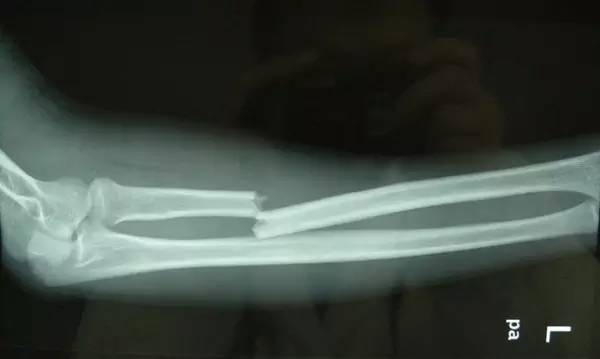

由于摔倒或者是其他情况,有可能造成骨折,骨折的时候不要自己随意动弹,应及时拨打120急救电话,等待医院救治。在路上碰到骨折的病人,也不要随意将病人扶起,可能造成更大的二次伤害。4.突然昏迷